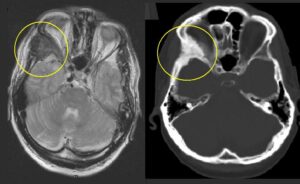

Segmentectomia con radioembolizzazione con ittrio-90 a base di resina (Y90-RE) con dosimetria secondo il Modello MIRD di un uomo di 72 anni con cirrosi da epatite C e un carcinoma epatocellulare (HCC) di 2,8 cm nel segmento 8.

(a) Immagine di Risonanza Magnetica (MRI) con soppressione del grasso in fase arteriosa T1 di una lesione epatica nel segmento 8. La punta di freccia bianca mostra il potenziamento del tumore.

(b) Cateterizzazione sotto-selettiva del ramo dell'arteria epatica che alimenta il tumore. La punta di freccia bianca mostra l'impregnazione (blush) del tumore con il mezzo di contrasto.

(c) Una Cone Beam CT (CBCT) "a secco" ha confermato una buona copertura del tumore al termine della procedura.

(d) La SPECT/CT fusa con tracciante di mappatura di tecnezio-99m macroaggregato (MAA) ha dimostrato un assorbimento soddisfacente nella lesione. Il volume del segmento 8 era di 197 mL. È stata presa la decisione di somministrare 27 mCi con microsfere di resina con 3 giorni di pre-calibrazione per raggiungere una dose di 250 Gy (Gray) all'angiosoma.

(e) Analisi dosimetrica post-trattamento tramite SPECT/CT di Bremsstrahlung di ittrio-90 con contorno del fegato normale (rosa) e contorno del tumore (rosso). La dose effettiva somministrata al tumore è risultata essere 472 Gy; la dose al fegato normale è stata di 37 Gy.

(f) Risonanza Magnetica (MRI) con soppressione del grasso in fase arteriosa T1 a 6 mesi dal trattamento. La punta di freccia bianca mostra una risposta completa nella zona del tumore. Le frecce bianche mostrano i cambiamenti post-trattamento nel parenchima epatico normale circostante.